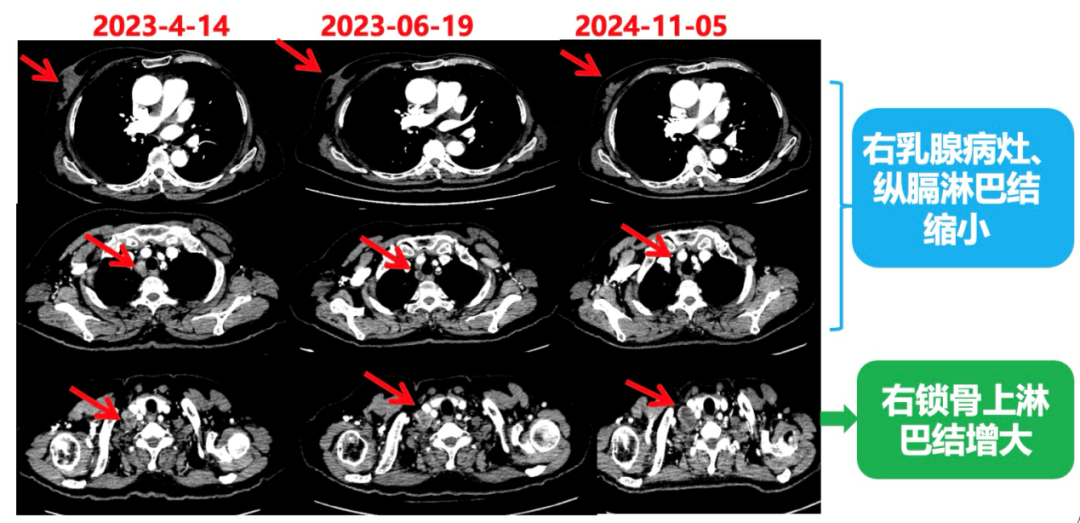

2023.6.26复查PET-CT

1.右乳外上象限乳腺癌病灶(22*16mm),对比2023-04-14 CT(26*24mm)较前缩小,FDG代谢活跃。右侧腋窝小淋巴结(5mm),较前稍缩小,代谢不活跃。右侧锁骨上区、上纵隔淋巴结转移瘤(24*18mm),现大小同前相仿,代谢活跃(SUV:6.7)。

2024-11-5复查CT:右乳外上象限占位(11mm×9mm),较前明显缩小;上纵隔及右肺门多发淋巴结转移缩小;右锁骨上区淋巴结较前增大。余部位未见肿瘤转移及复发征象。

患者右锁骨上淋巴结较前增大,乳腺病灶明显缩小,针对是否需要进行锁骨上淋巴结及乳腺手术,龚畅教授和曾银朵教授又组织了第三次多学科会诊。

影像科:CT显示右侧锁骨上区病灶增大主要表现为液化坏死改变,考虑为治疗后改变而非肿瘤进展所致。